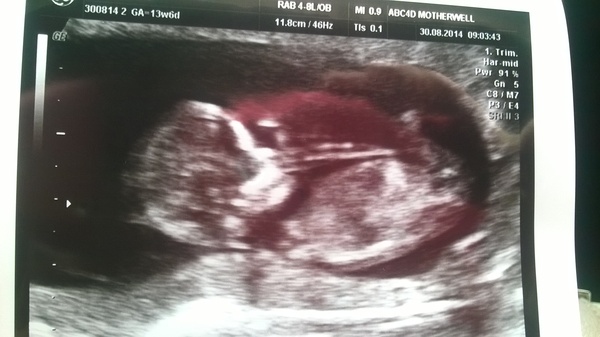

Reassurance scan went well today - turns out I'm much further on than I thought at just over 12 weeks. Although scan pic says 13w 4d, so why would she have said 12?

I'll try post my scan pic :) swear I can see wee boys bits, or its just wishful thinking lol

Beany

gudgy great scan pic! You must be relieved!

Thank u pinksun! He waved his wee arm during it and I just broke down lol was like he was saying hello! Just feel silly I've got so far on without noticing

Lovely scan pic Gudgy.